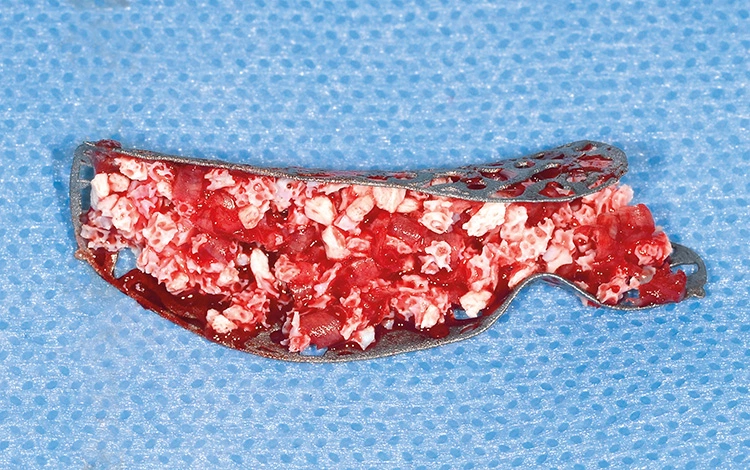

Trotz der schlechten, hart- und weichgewebigen Grundvoraussetzungen konnte der Kieferkamm zufriedenstellend rekonstruiert werden. Die Augmentation des kombinierten, horizontalen und vertikalen Defekts mit Yxoss CBR®, Geistlich Bio-Oss®, Geistlich Bio-Gide®, autologem Knochen und PRF ermöglichte die Implantation mit hoher Primärstabilität in den rekonstruierten Bereich.